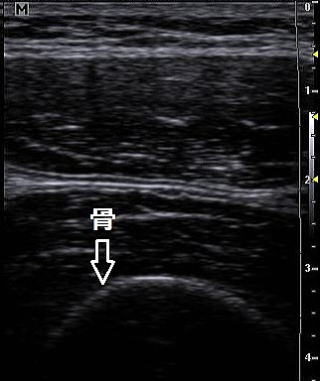

正常の骨ライン            骨折のライン

骨